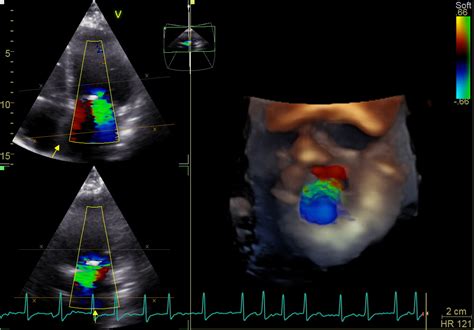

- Examinări de specialitate cardiologie pediatrică - inclusiv ecografie Doppler pentru depistarea malformațiilor cardiace

În cadrul consultațiilor de cardiologie pediatrică, se abordează cu prioritate malformațiile congenitale de cord la toate vârstele, de la nou-născut la adolescent. De asemenea, sunt tratate afecțiunile cardiovasculare dobândite, precum hipertensiunea arterială și tulburările de ritm la copil.

- Competențe: Ecocardiografie DOPPLER color